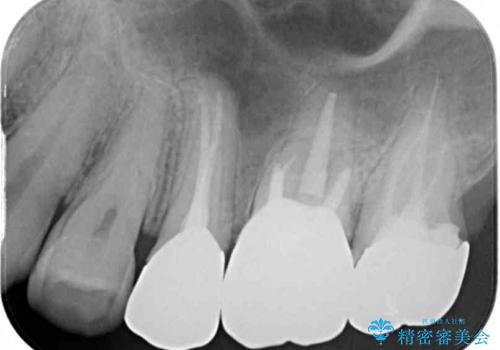

治療後すぐに痛みが引き、治療後半年が経過した際のレントゲン写真では、排膿の元となっていた、歯根先端の病変の消失が認められました。